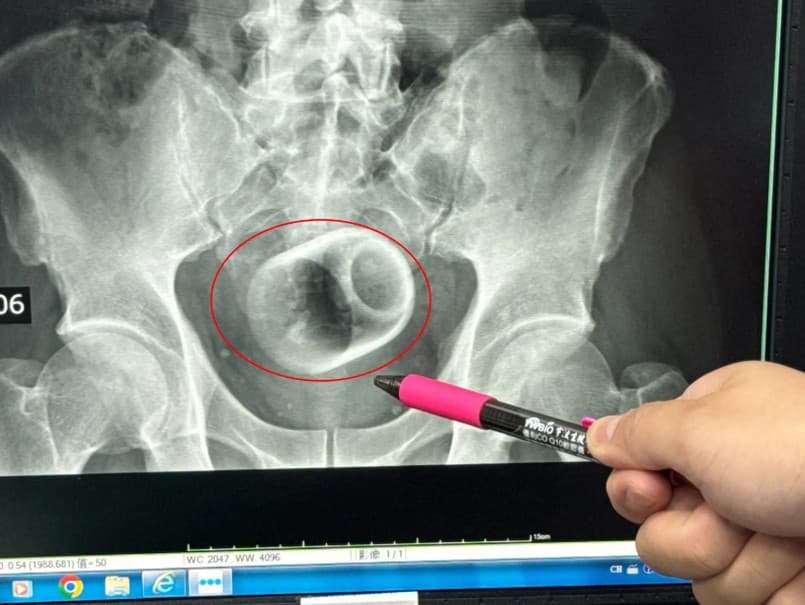

V taiwanskom meste Tchaj-čung sa odohral prípad, ktorý prekvapil aj skúsených lekárov. Muž, ktorého vek miestne médiá neuviedli, trpel tri dni zápchou a silnými bolesťami brucha. Keď sa jeho stav začal rýchlo zhoršovať, rozhodol sa vyhľadať odbornú pomoc. Ako informuje magazín The Sun, v nemocnici podstúpil sériu vyšetrení, vrátane röntgenu. Ten odhalil dôvod jeho ťažkostí... v konečníku mal uviaznutý keramický hrnček široký približne šesť centimetrov a vysoký osem centimetrov.

Lekársky tím sa najprv pokúsil hrnček vybrať pomocou nástrojov, no hladký keramický povrch manipuláciu znemožňoval. Zvažovali aj laparoskopický zákrok, avšak existovala obava, že by sa hrnček mohol rozbiť a spôsobiť závažné komplikácie, ako krvácanie či infekciu. Medzitým sa časť čreva začala poškodzovať v dôsledku nedostatočného prekrvenia.